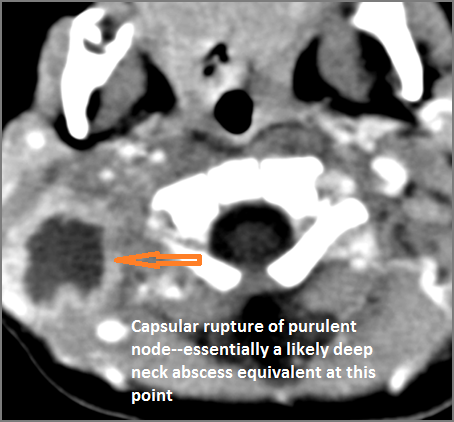

If there is suppurative cervical adenopathy the purulent material outside the lymph node(s) capsule(s).